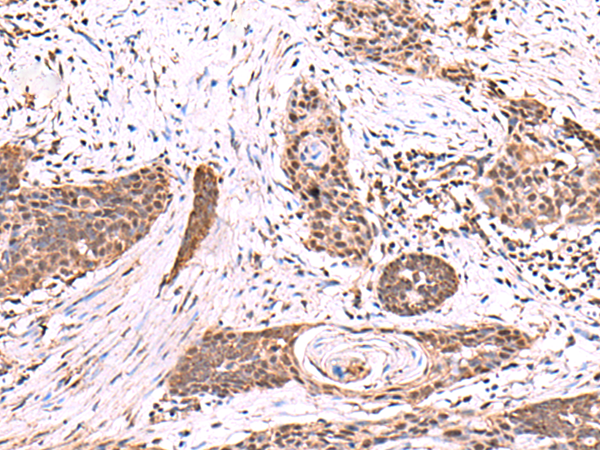

IHC positive control:

Human tonsil and Human esophagus cancer

IHC Recommend dilution:

50-300